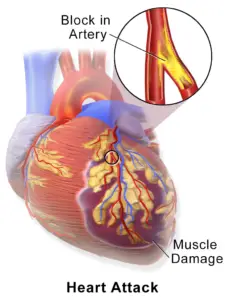

Coronary artery disease is the primary cause of most heart attacks, resulting from the blockage of one or more coronary arteries due to cholesterol-laden deposits known as plaques.

These plaques can narrow the arteries, leading to reduced blood flow to the heart. If a plaque ruptures, it can trigger the formation of a blood clot in the heart.

Heart attacks can be categorized based on whether an electrocardiogram (ECG or EKG) reveals specific changes (ST elevation) necessitating urgent invasive treatment.

- An acute complete blockage of a medium or large coronary artery is typically diagnosed as an ST elevation myocardial infarction (STEMI).

- A partial blockage often corresponds to a non-ST elevation myocardial infarction (NSTEMI), although some individuals with NSTEMI may have a total blockage.